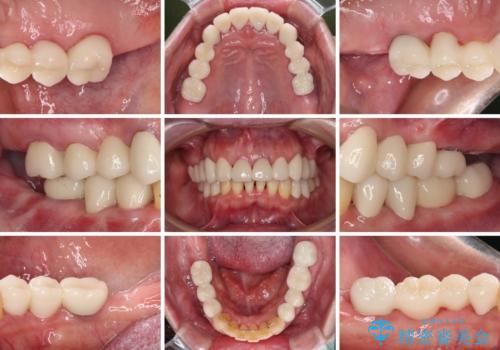

インプラントに対する恐怖心が強く、欠損補綴は極力ブリッジを採用し、インプラントの数は必要最小限としました。

油断をするとすぐに汚れが溜まって歯肉が腫れてきてしまうため、今後も定期的なメインテナンスが重要となります。